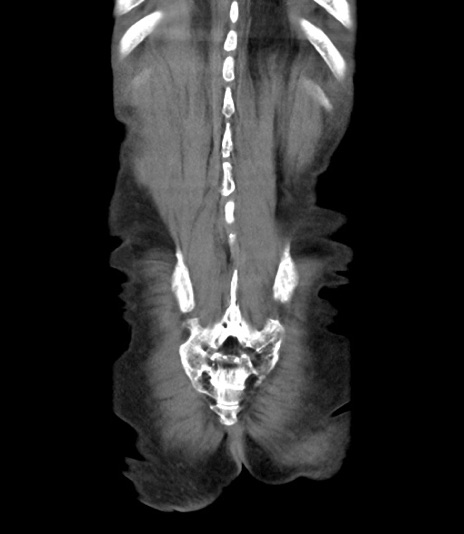

矢状断像

【症例】 70歳代男性

【主訴】右鼠径部腫瘤、疼痛

【現病歴】本日朝より上記主訴あり、受診。

【既往歴】膀胱癌にて膀胱全摘、両側尿管皮膚瘻

【データ】WBC 5600、CRP 0.56